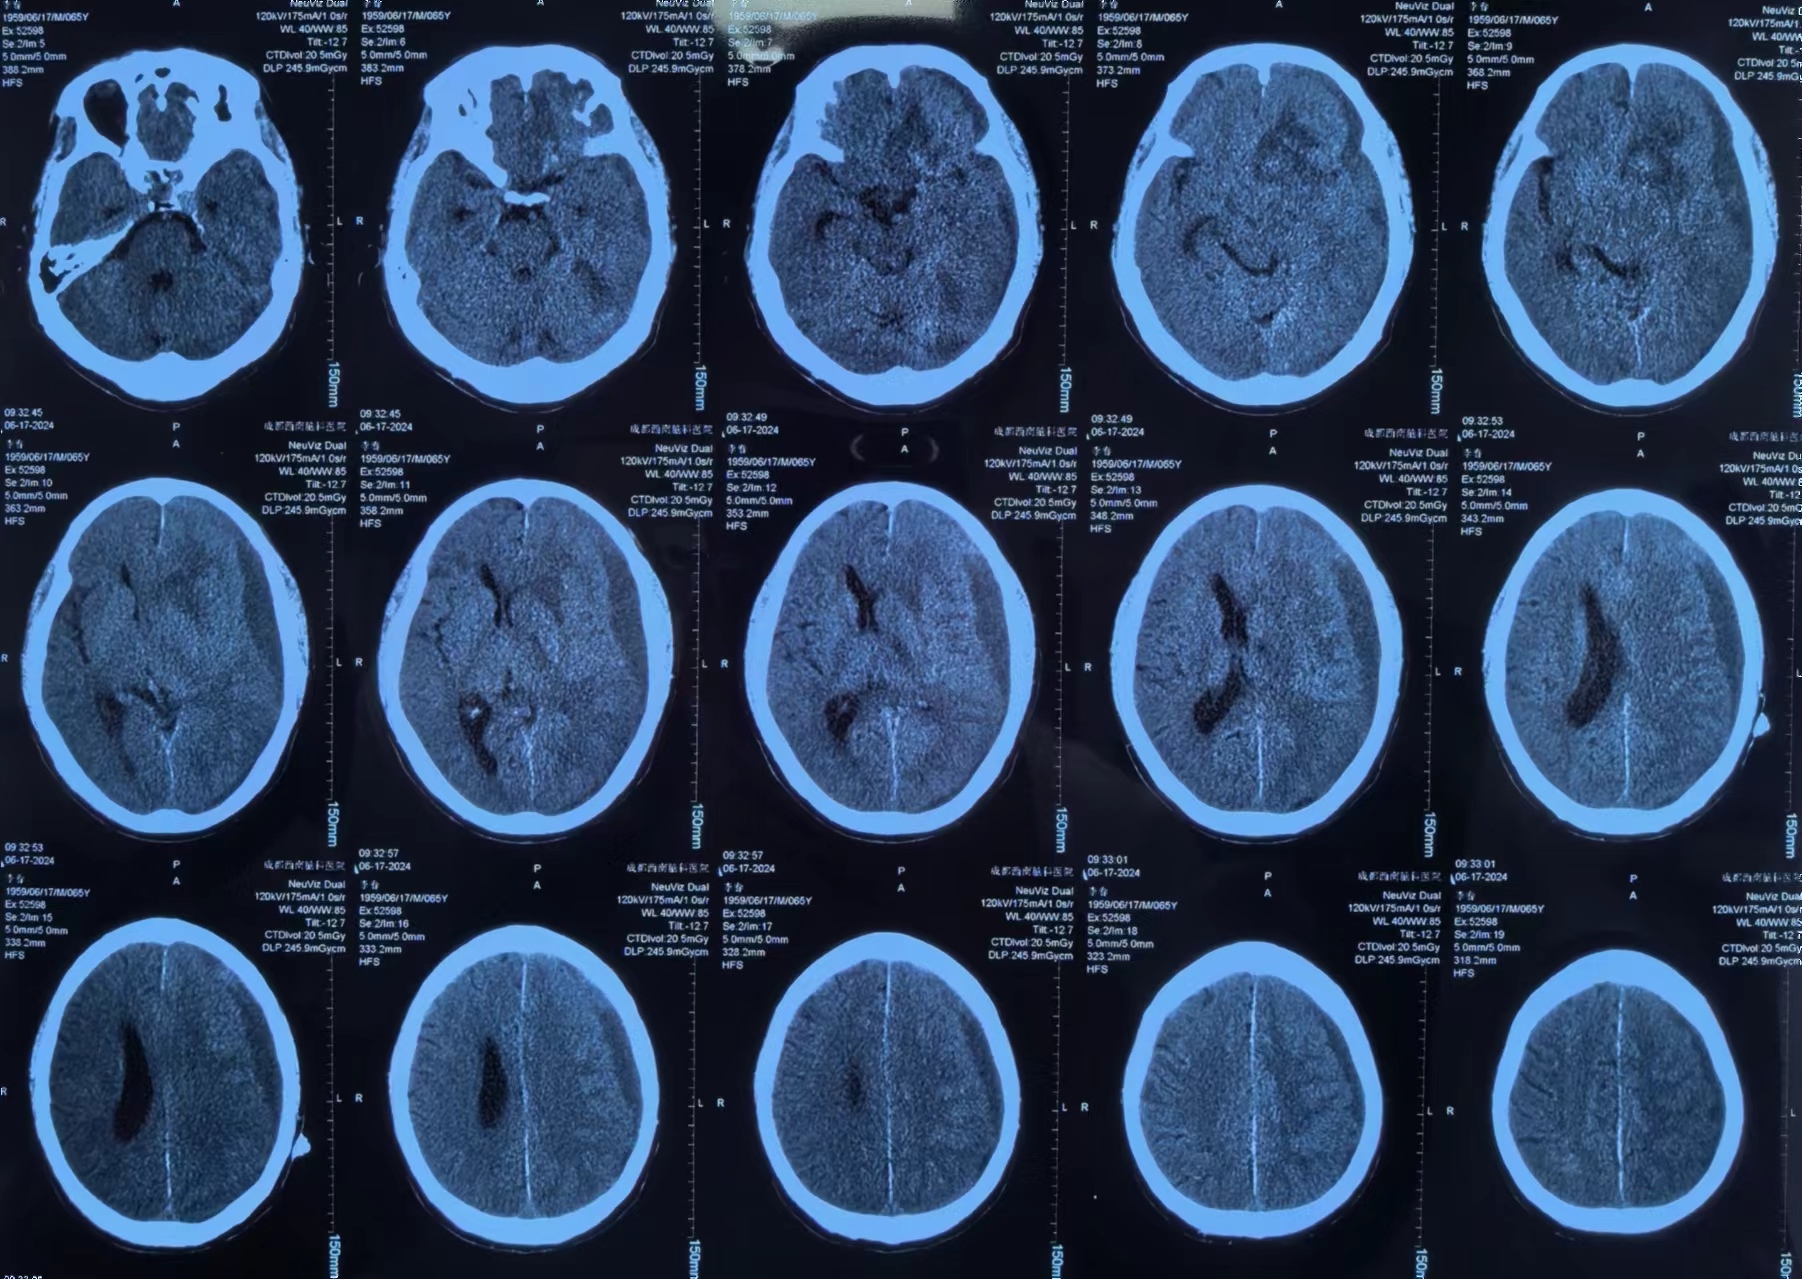

李先生有高血压病史3+年,最高血压166/88mmHg,血压控制一般。10+天前突然出现意识丧失,立即就诊当地医院。李先生送医途中就恢复了意识,但全头部爆炸样胀痛,诊断为脑出血、硬膜下血肿、蛛网膜下腔出血,大脑前动脉中度狭窄,颈内及大脑中动脉均发现动脉瘤。

因当地医院对症治疗一周效果不佳,为求进一步治疗,家人带着李先生辗转来到我院。经左剑主任与李积荣主任联合会诊,认为李先生目前的头痛主要与脑内血肿引起的脑水肿及硬膜下血肿引起的颅高压有关。因患者有多发颅内动脉瘤,最终决定局麻下采用“颅内血肿微创清除技术”清除硬膜下血肿。

李先生手术前

术后李先生自觉头痛明显减轻,术后第三天复查头颅CT提示:硬膜下血肿基本清除,脑移位恢复正常。